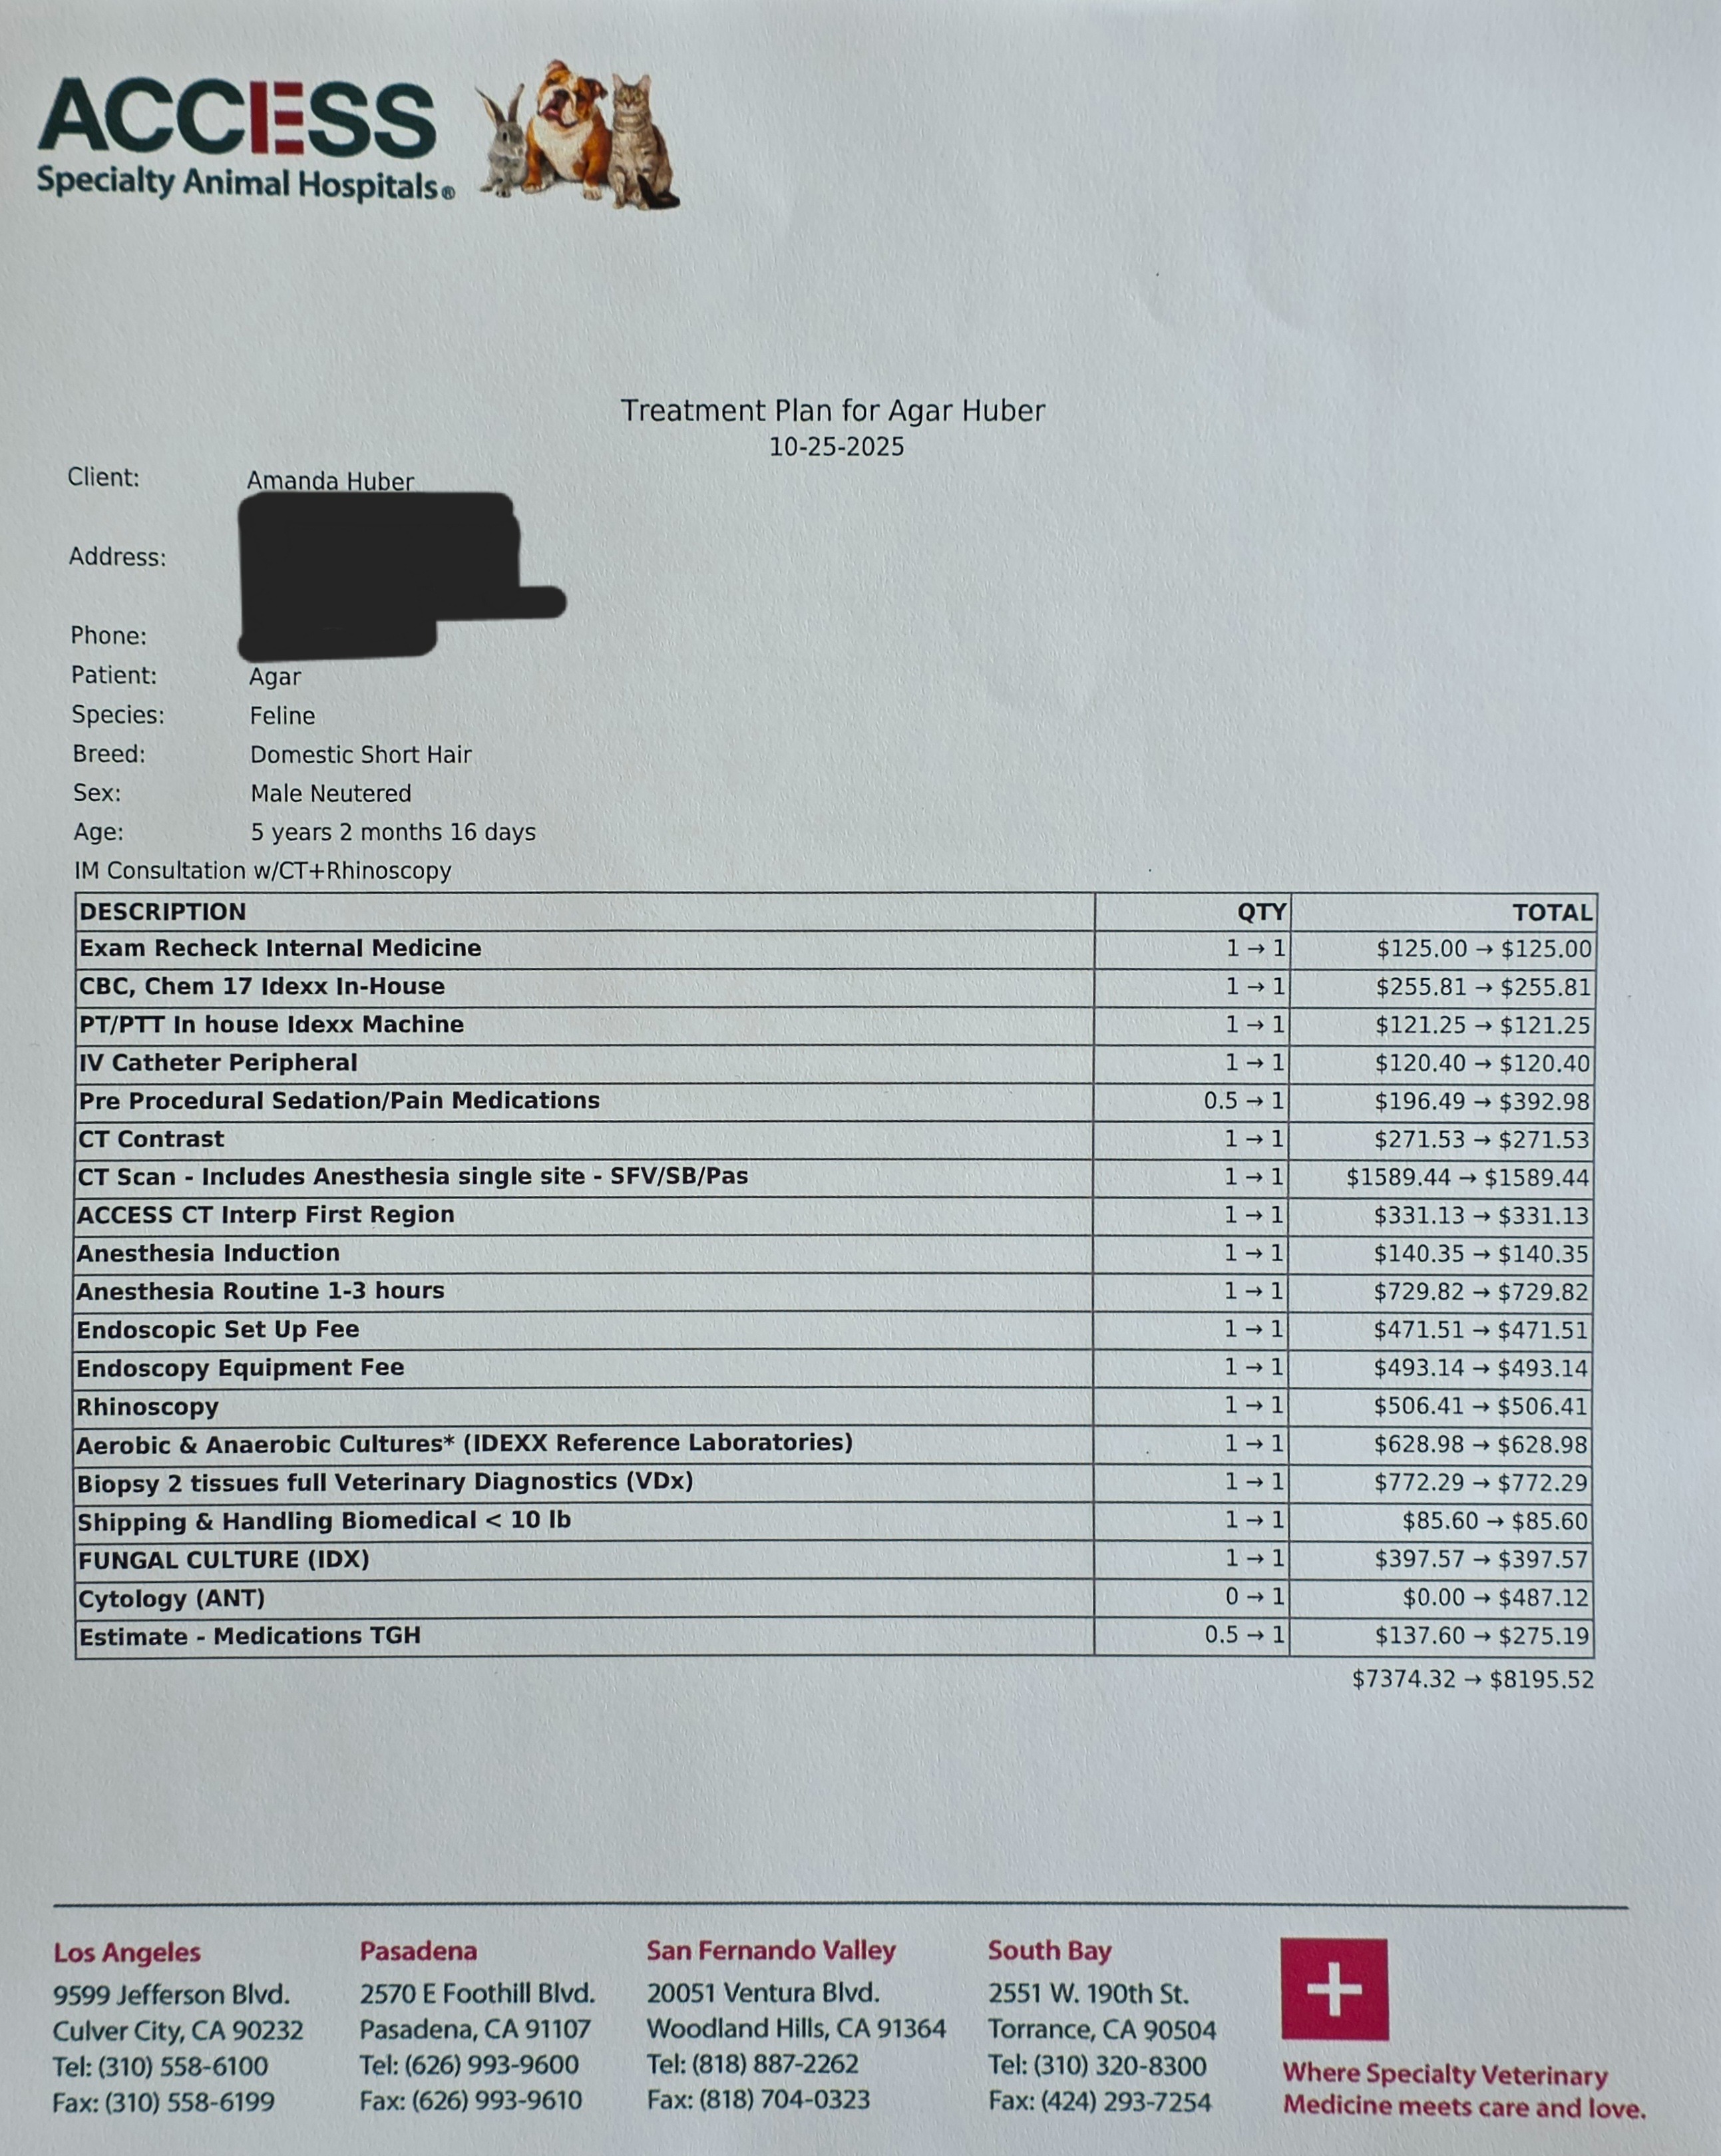

I'm raising funds for my cat Agar's medical bills. He has been dealing with a mystery mass on his nose for about a year now. Two regular vets, four specialty vets, and one emergency vet later, and no real answers have been reached. We're sending him in for some exploratory care to hopefully find out what our next steps could even be. He will be getting the care he needs no matter how much is raised; whatever needs to be done will be done, but anything will help.